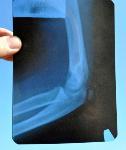

В ОУ "Христо Ботев" в хасковското село Динево по време на учебен час на 20-ти февруари 63-годишната учителка Виолета Николова Панайотова е въдворила ред в клас с помощта на дръжка от метла. Със своеобразната тояга дълга около 1,50 метра преподавателката е ударила през ръцете петокласника Огнян Мишев и му е нанесла вътрешна травма на лакътната става на дясната ръка - епифизиолиза. Детето е освидетелствано от съдебен лекар в МБАЛ Хасково. Ръката е гипсирана. Учителката Николова е уволнена, а родителите Янко и Христина заявиха, че ще я съдят. Директорът на училището Ясен Колязов е изгорил въпросната пръчка. Учителката обяснила на Колязов, че е рикоширал удар в ръката на детето. 27.02.2014 |